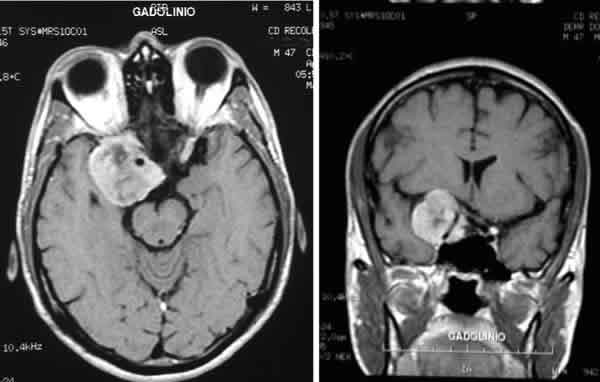

Fig. 1. RMN (cortes axial y coronal; imagen potenciada en T1, con gadolinio): muestra una masa que presenta calcificaciones y capta contraste (probable meningioma esfenoidal).

Las pruebas de imagen, solicitadas por el Servicio de Neurocirugía demostraron la presencia de una masa en el seno cavernoso. Se trataba de una masa con base de implantación en la apófisis clinoides anterior y el ala mayor del esfenoides, que erosionaba la fisura orbitaria superior, el seno esfenoidal y la silla turca. Tanto su localización como la presencia de calcificaciones, y el hecho de que captara contraste, hacían pensar que se trataba de un meningioma.